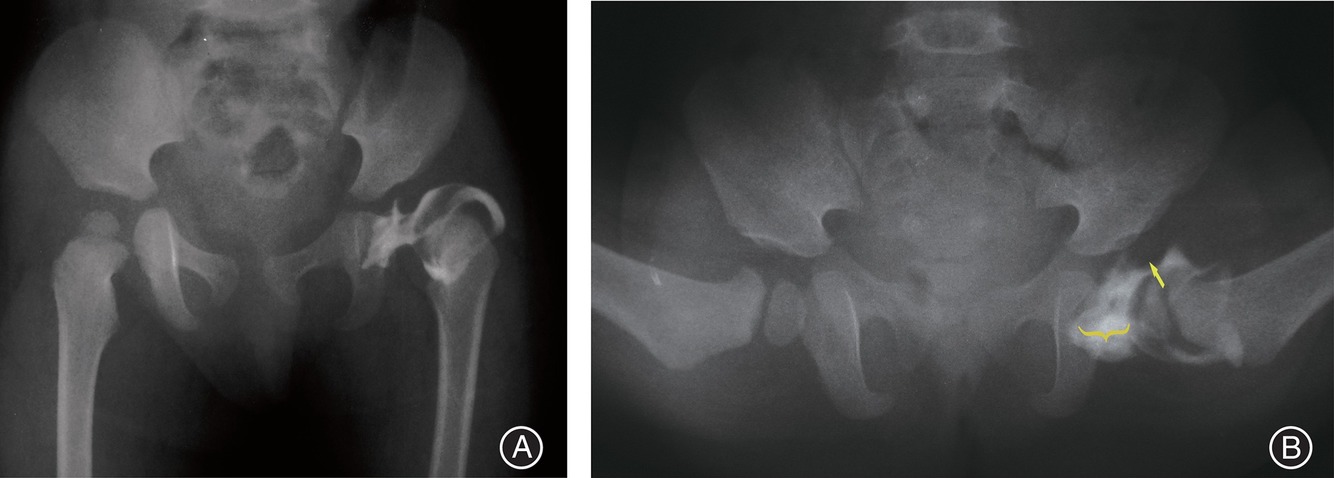

1. Describe image on the left.

Plain radiograph of pelvis of a skeletally immature child with DDH with a dislocated hip as highlighted by arthrogram which showed

- medial pooling > 7mm

- hour-glass configuration of the capsule

- Rose thorn sign Limbus

2. What is the procedure being done?

Closed reduction of a dislocated hip in a skeletally immature child with DDH, aided by arthrogram to confirm if the femoral head is concentrically reduced into the acetabulum.

- need to obtain < 5 mm constrast pooling medial to femoral head, no interposition of the limbus.